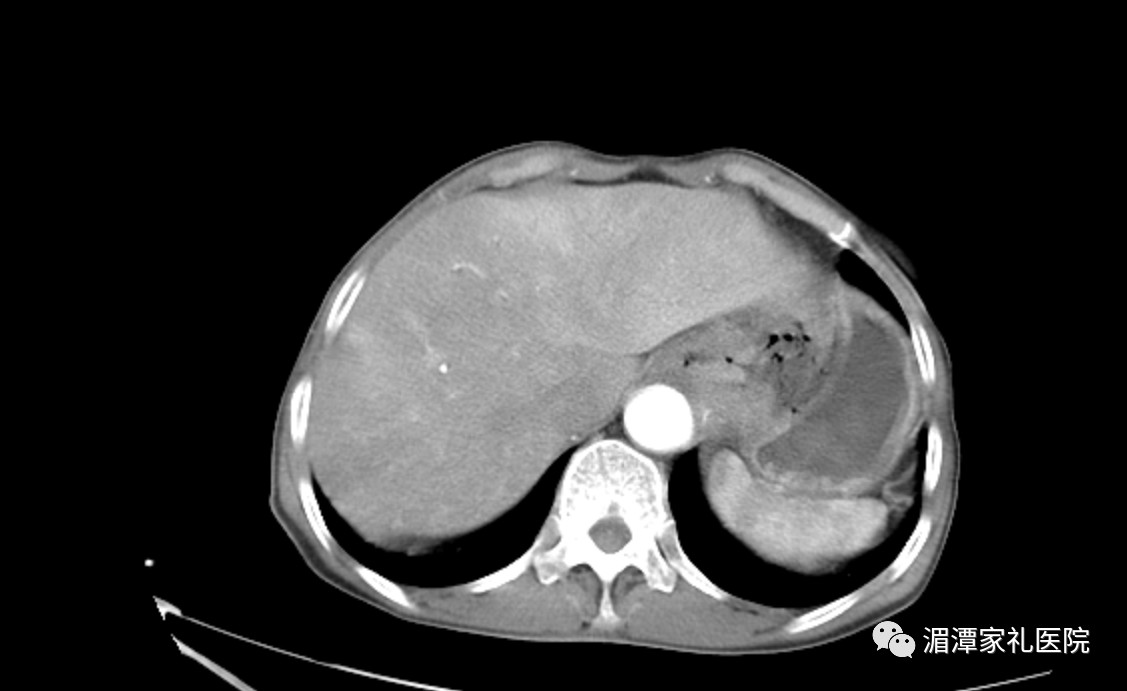

术后影像

就在术后6天(11月17号),唐婆婆迎来了自己70大寿,胸部疾病诊疗中心医护团队与她的家人一起为她庆祝了生日,老人十分开心。